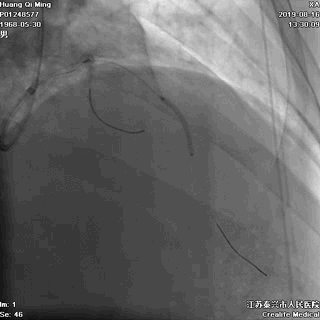

8atm,2.0*10 切割球囊对斑块进行切割

16atm,NC球囊对斑块进行预处理

2.0*25 药物洗脱球囊,8atm*60秒释放药物

2.5*25 药物洗脱球囊,8atm*60秒释放药物